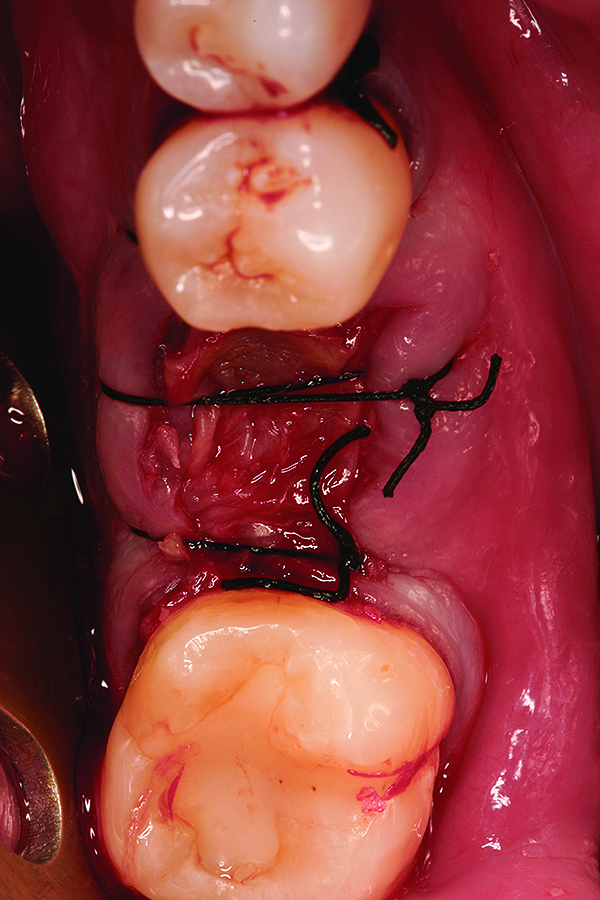

Fig 4. Intentional non-primary closure of surgical sites.

Figure 4

Fig 11. Intentional non-primary closure following the placement of an amnion-chorion barrier over the bone allograft.

Figure 11